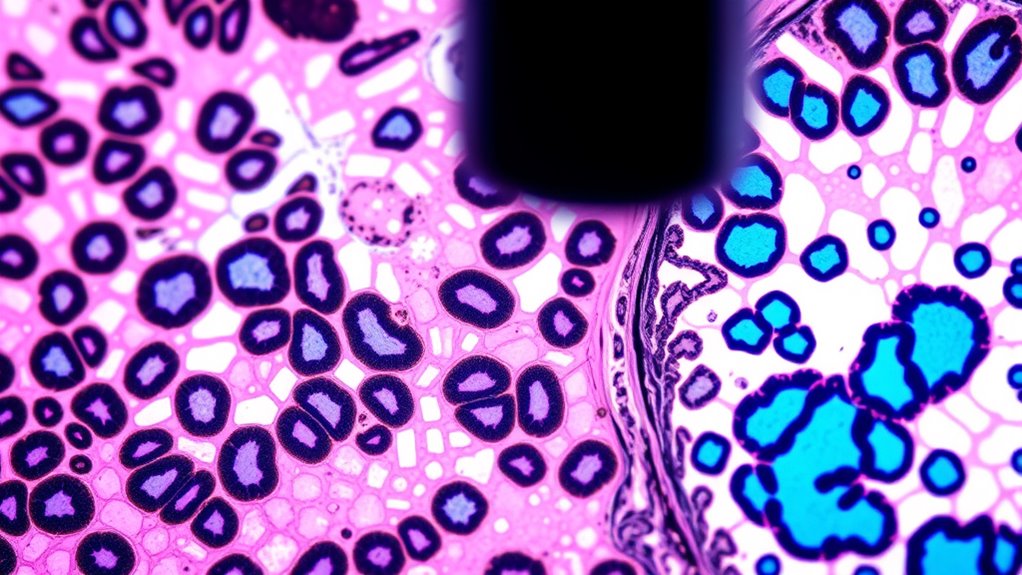

Ki-67 ist ein nukleäres Protein, das angibt, wie schnell Tumorzellen sich teilen, und liefert so einen Schnappschuss des Tumorwachstums. Wenn die Ki-67-Werte hoch sind, bedeutet dies, dass Ihre Tumorzellen sich schnell teilen, was oft auf ein aggressiveres Krebs hinweist. Umgekehrt deutet ein niedriger Ki-67-Wert auf ein langsamer wachsendes Tumorwachstum hin und kann eine bessere Prognose bedeuten. Die Messung von Ki-67 hilft Ihnen zu verstehen, wie aggressiv Ihr Krebs sein könnte, und beeinflusst Behandlungsentscheidungen, wie zum Beispiel, ob eine Chemotherapie notwendig ist. Bedenken Sie, dass die Ki-67-Werte zwischen Primärtumoren und Metastasen variieren können, was Auswirkungen auf die Prognose und die Therapieentscheidungen haben kann. Im Allgemeinen sind höhere Ki-67-Werte mit größeren Tumoren, höherem Tumorgrad und einem höheren Rückfallrisiko verbunden, weshalb dieser Marker wertvoll für die Beurteilung des Tumorverhaltens ist.